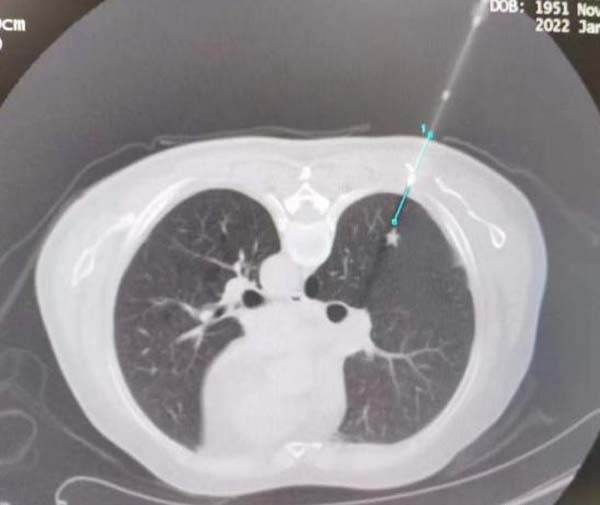

考虑到患者高龄,长期吸烟史,肺大疱,反复自发性气胸,肺功能差,难以行外科手术切除。应急总医院呼吸与危重症医学科主任周云芝带领团队综合分析患者病情,运用当今先进的多技术综合诊疗技术,为该患者制定了“一次性”诊疗方案——经皮同轴套管肺穿刺活检+微波消融术。

一次穿刺即能活检又能消融结节,微创操作,损伤小,减少因多次穿刺引起患者不适及并发症的发生。

设计穿刺路径: